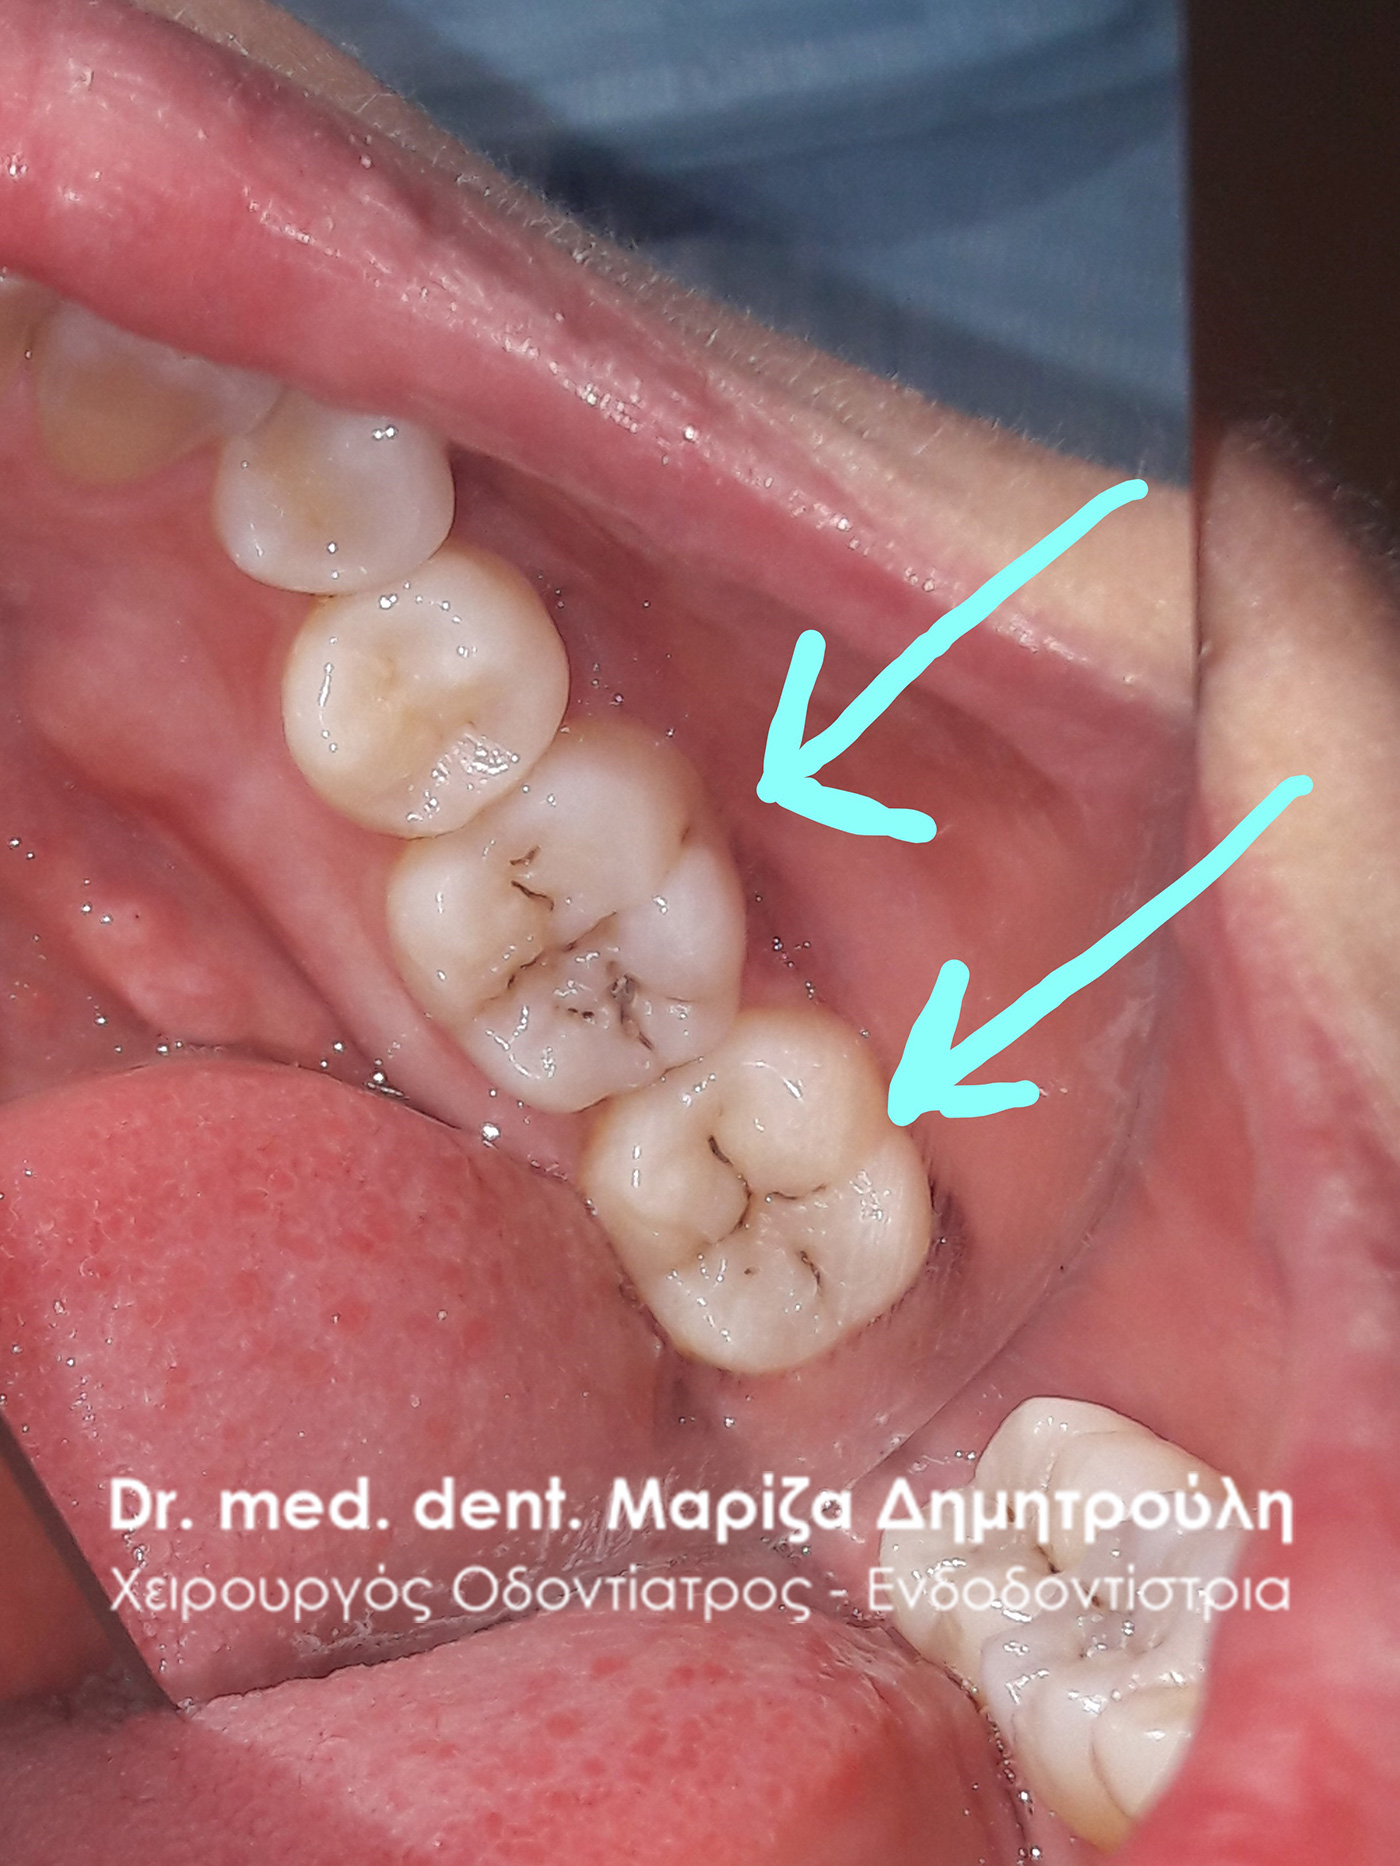

Περιστατικό – Ολική αποκατάσταση σφραγισμάτων δοντιών

Η ασθενής προσήλθε στο ιατρείο με σκοπό να αντικαταστήσει κάποια παλιά σφραγίσματα, τα οποία περιστασιακά της έδιναν συμπτώματα πόνου. όπως δείχνουν οι φωτογραφίες τα δόντια αποκαταστάθηκαν με νέα λευκά σφραγίσματα.

ΠΡΙΝ

Αρχική εικόνα κάτω αριστερών γομφίων